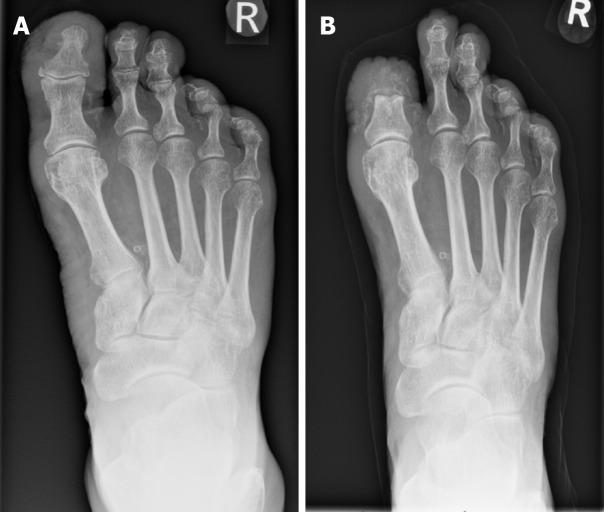

The prevalence of diabetes mellitus and its associated complications, particularly diabetic foot pathologies, poses significant healthcare challenges and economic burdens globally. This review synthesises current evidence on the surgical management of the diabetic foot, focusing on the interplay between neuropathy, ischemia, and infection that commonly culminates in ulcers, infections, and, in severe cases, amputations. The escalating incidence of diabetes mellitus underscores the urgency for effective management strategies, as diabetic foot complications are a leading cause of hospital admissions among diabetic patients, significantly impacting morbidity and mortality rates. This review explores the pathophysiological mechanisms underlying diabetic foot complications and further examines diabetic foot ulcers, infections, and skeletal pathologies such as Charcot arthropathy, emphasising the critical role of early diagnosis, comprehensive management strategies, and interdisciplinary care in mitigating adverse outcomes. In addressing surgical interventions, this review evaluates conservative surgeries, amputations, and reconstructive procedures, highlighting the importance of tailored approaches based on individual patient profiles and the specific characteristics of foot pathologies. The integration of advanced diagnostic tools, novel surgical techniques, and postoperative care, including offloading and infection control, are discussed in the context of optimising healing and preserving limb function.

糖尿病及其相关并发症,尤其是糖尿病足病变的患病率,在全球范围内构成了重大的医疗挑战和经济负担。本综述综合了关于糖尿病足手术治疗的现有证据,重点关注神经病变、缺血和感染之间的相互作用,这些因素通常最终导致溃疡、感染,严重时还会导致截肢。糖尿病发病率的不断上升凸显了有效管理策略的紧迫性,因为糖尿病足并发症是糖尿病患者住院的主要原因,对发病率和死亡率有重大影响。本综述探讨了糖尿病足并发症的病理生理机制,并进一步研究了糖尿病足溃疡、感染和夏科关节病等骨骼病变,强调了早期诊断、综合管理策略和跨学科护理在减轻不良后果方面的关键作用。在讨论手术干预措施时,本综述评估了保守手术、截肢和重建手术,强调了根据个体患者情况和足部病变的具体特征采取定制方法的重要性。在优化愈合和保留肢体功能的背景下,讨论了先进诊断工具、新型手术技术和术后护理(包括减负和感染控制)的整合。